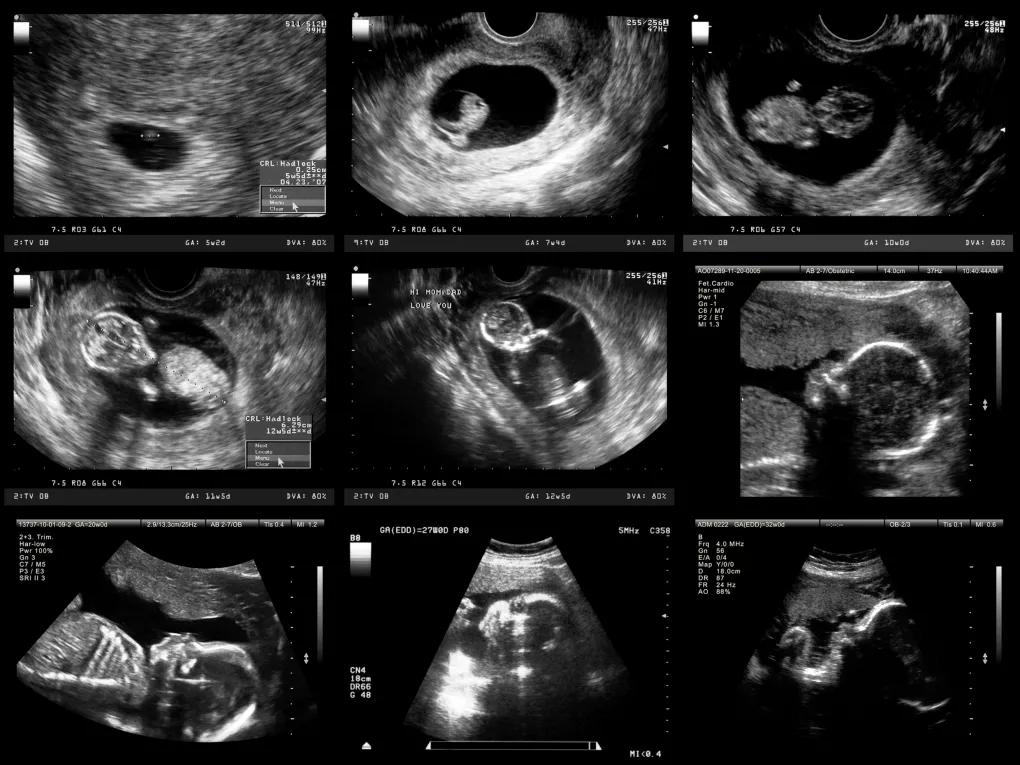

Kann ich die Grösse meines Babys im Ultraschall sehen?

Ja, die Grösse des Embryos kann im Ultraschall gemessen werden. Der Arzt kann anhand der Grösse des Embryos das Schwangerschaftsalter bestimmen und die Entwicklung des Kindes kontrollieren.